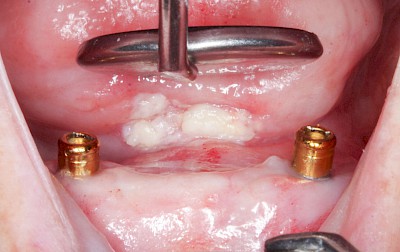

Metalltätowierung

Häufig zu beobachten sind einzelne dunkle Flecken im Nahbereich der Zähne. Häufig handelt es sich dabei um Amalgam- oder Metall-Tätowierungen. Bei zahnärztlichen Behandlungen kann es zur "Versprengung" von Metall-Anteilen von Füllungen oder Kronen kommen. Diese lagern sich dann reizlos in die Schleimhaut ein.